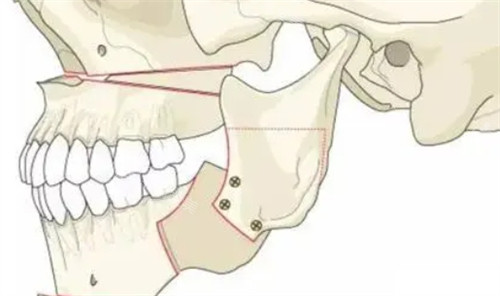

这些影像资料会被录入三维建模系统,医师会结合我的咬合数据、日常咀嚼习惯以及我对面部轮廓的诉求,逐毫米拆解颌骨需要调整的方向和幅度,而非给出一套标准化的方案。这份定制化的规划里,甚至标注了术中下颌骨移动的具体数值、上颌骨调整的角度,让我清晰知晓手术的每一个核心环节。

手术短时间内,进入手术室前的然后十分钟,医师仍拿着方案和我确认细节,用简单的中文词汇搭配手势,缓解我紧绷的情绪。整个手术采用的是经口内入路的操作方式,所有切口都隐藏在口腔内部,从根源上避免了面部留疤的可能,这也是我当初选择赴韩做这项手术的重要考量之一。